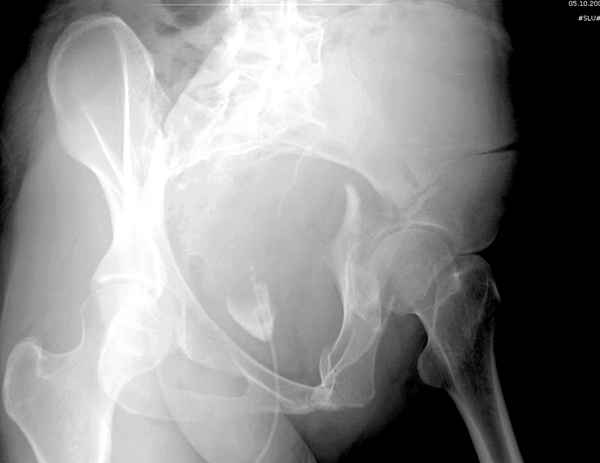

Все выступающие коллеги высказались насчет необходимости стандартных снимков по Judet, потому что для определения тактики лечения переломов вертлужной впадины 3Д снимки малоинформативны.

Летурнель разработал классификсацию на основании прямого, запирательного и подвздошного рентген снимков, котоые, кроме описания характера переломов, также подсказывают адекватный доступ для репозиции перелома.

Из того минимума, что представлено, мне кажется, мы имеем дело с двухколонным переломом вертлужной впадины. Обычно медиальный (центральный) "вывих" головки встречаются в сложных двухколонных переломах со смещением.